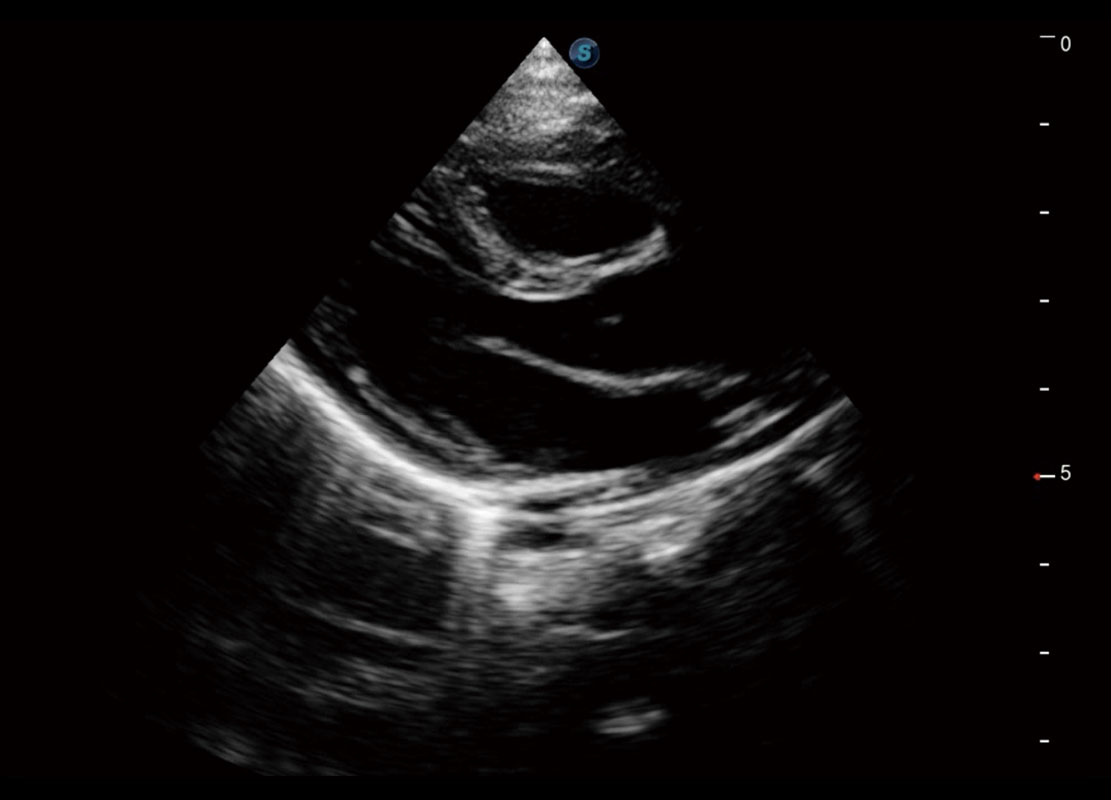

P60搭载一系列胎儿心脏成像技术,实现精细的胎儿心脏评估。

四腔切面